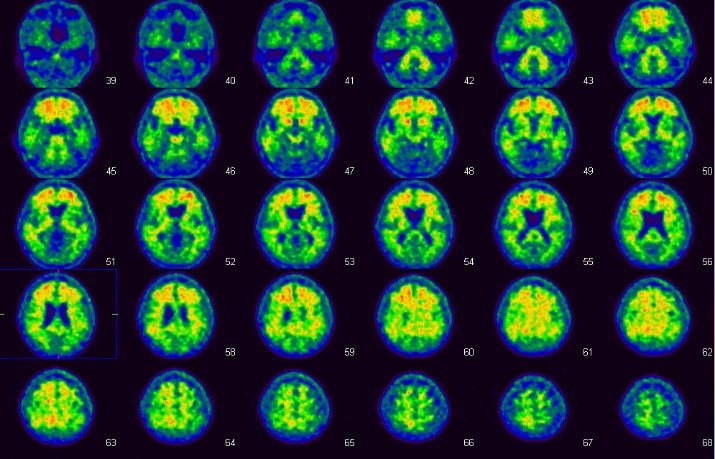

FDG-PET検査

この検査は、てんかんの病巣診断、心サルコイドーシスの診断、早期胃がんを除く全ての悪性腫瘍・悪性リンパ腫の診断等に有用とされています。当院では主にてんかんの方の検査を多く行っていますが、その他の上記疾患の検査も行っています。

使用する放射性医薬品は18F-FDGです。当院では投与直前から調光下で安静にベッドに横になっていただき、投与後は頭部検査では45分後から15分程度、全身では60分後から30分程度、心臓では全身の撮像後に15分程度の撮像を行います。